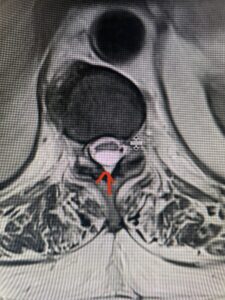

Fig 2a Sagittal and axial T2 weighted cervical MRIs demonstrating large C4 5 herniated disc with spinal cord compression red arrows

This 47-year-old male who four months prior was lifting weights developed sharp pain in his neck. After that he developed progressive numbness in his arms, neck pain and headache. He said that the right arm was worse than the left. On examination the patient had long tract weakness on the right side which included his triceps, finger extensors, hip flexors, and dorsiflexors. The patient did not have hyperreflexia. MRI (Fig. 2) demonstrated a massive, extruded disc herniation with severe cord compression. The patient because of progressive myelopathy and spinal cord compression was indicated for anterior cervical discectomy and fusion at C4-5 (Fig. 3). Patient had significant improvement of weakness and numbness post operatively.

Fig. 2a Sagittal T2-weighted cervical MRI demonstrating large C4-5 herniated disc with spinal cord compression (red arrow)

Fig: 2b Axial T2-weighted cervical MRI demonstrating spinal cord compression from C4-5 herniated disc (red arrow)